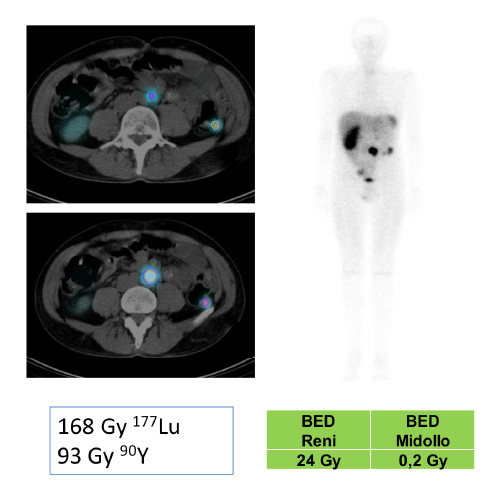

La velocità di progressione della fibrosi cardiaca: un nuovo orizzonte

La velocità di progressione della fibrosi cardiaca emerge come un nuovo e cruciale indicatore prognostico nella cardiomiopatia ipertrofica. Un recente studio evidenzia come l’LGE rate sia più predittivo degli eventi avversi rispetto alla semplice estensione della fibrosi, aprendo nuove prospettive per il monitoraggio e la gestione terapeutica dei pazienti.